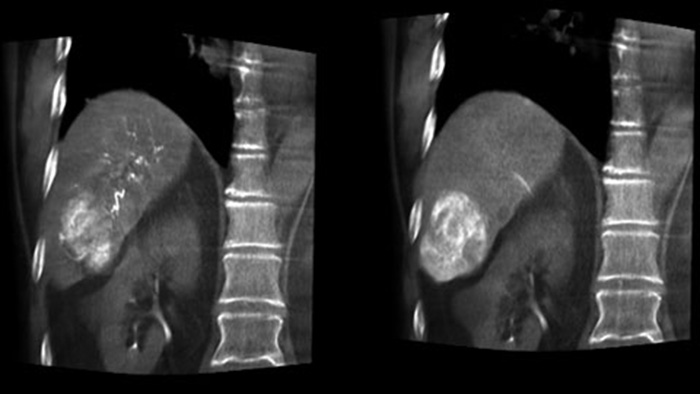

Optimisation de la visualisation des artères et des tumeurs avec CBCT double affichage

Visualisation optimale des artères et des tumeurs avec CBCT double affichage

La fonction CBCT double affichage permet l’acquisition 3D d’une phase artérielle pour visualiser les structures vasculaires et d’une phase post-artérielle (phase retardée) pour visualiser l’accumulation du produit de contraste, en une seule étape automatique.5